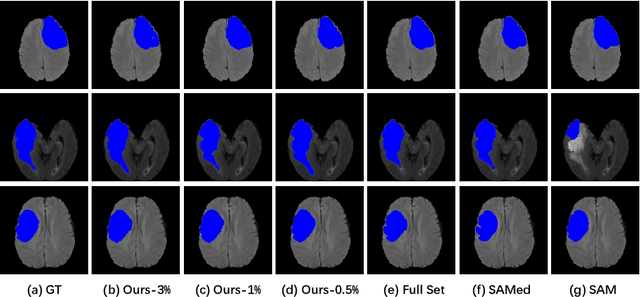

Abstract:The Segment Anything Model (SAM) has demonstrated remarkable capabilities of scaled-up segmentation models, enabling zero-shot generalization across a variety of domains. By leveraging large-scale foundational models as pre-trained models, it is a natural progression to fine-tune SAM for specific domains to further enhance performances. However, the adoption of foundational models in the medical domain presents a challenge due to the difficulty and expense of labeling sufficient data for adaptation within hospital systems. In this paper, we introduce an efficient and practical approach for fine-tuning SAM using a limited number of exemplars, making it suitable for such scenarios. Our approach combines two established techniques from the literature: an exemplar-guided synthesis module and the widely recognized Low-Rank Adaptation (LoRA) fine-tuning strategy, serving as data-level and model-level attempts respectively. Interestingly, our empirical findings suggest that SAM can be effectively aligned within the medical domain even with few labeled data. We validate our approach through experiments on brain tumor segmentation (BraTS) and multi-organ CT segmentation (Synapse). The comprehensive results underscore the feasibility and effectiveness of such an approach, paving the way for the practical application of SAM in the medical domain.